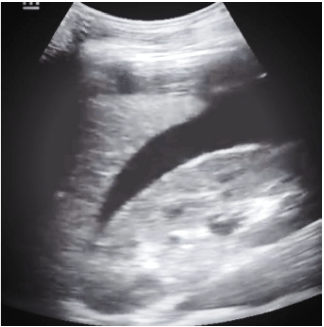

Paciente masculino de 18 anos com história de agressão física com chutes na região abdominal. Na avaliação inicial, observa-se pulsos cheios e rítmicos, e boa perfusão periférica, sem sudorese ou palidez, frequência cardíaca de 78bpm e saturação de O2 de 97% em ar ambiente. O esfigmomanômetro não está disponível. Realizado um FAST (focused assessment with sonography for trauma), que identifica a imagem abaixo. Qual alternativa contempla a conduta mais adequada nesse momento?